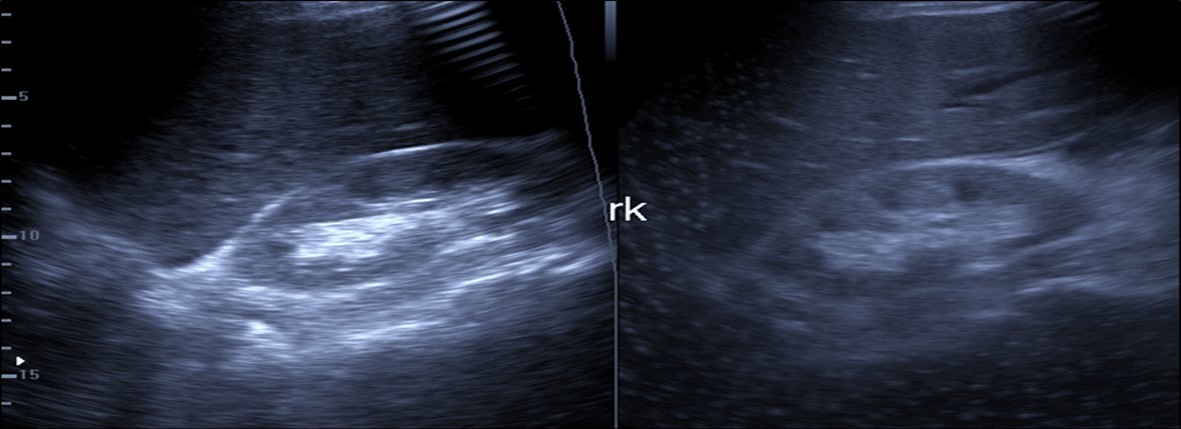

Abdominal ultrasound may revealed any of the followings:-Mild hepatomegaly with echogenic parenchyma and ascites in cases with hepatic impairment (Figure 4, Figure 5) ,thick walls of gall bladder with mildly dilated Common bile duct suggesting of biliary stasis and cholecystitis (Figure 6) .Abnormal renal echogenicity (Figure 7), suprarenal gland enlargements with heterogeneous texture ,splenic wedge shape area of hypoechogenicity ,thickened walls of bowel mainly the rectosigmoid region ,dilated bowel loops with free peritoneal fluid, and gases in the bowel wall with mesenteric and portal vein gases suggesting of bowel wall infarction13.

Figure 7.Patient with Covid-19 showing an echogenic kidney (rk) by ultrasound.